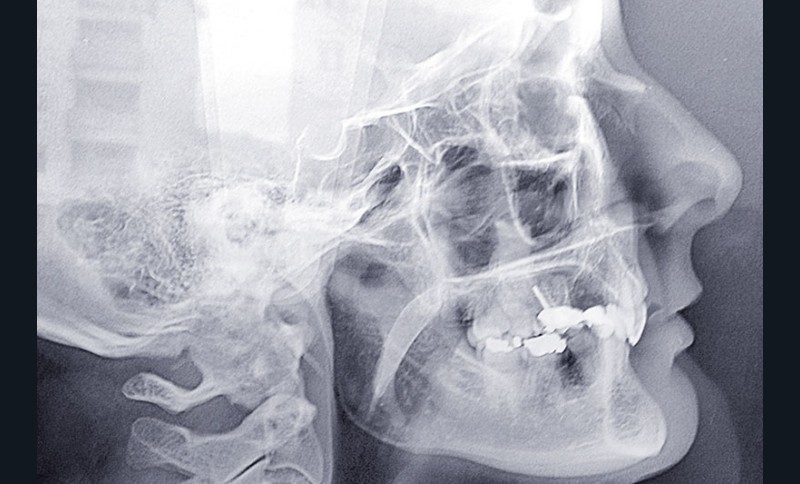

Malocclusion de classe II par rétrognathie mandibulaire dans un schéma squelettique hypodivergent (fig. 4 à 6).